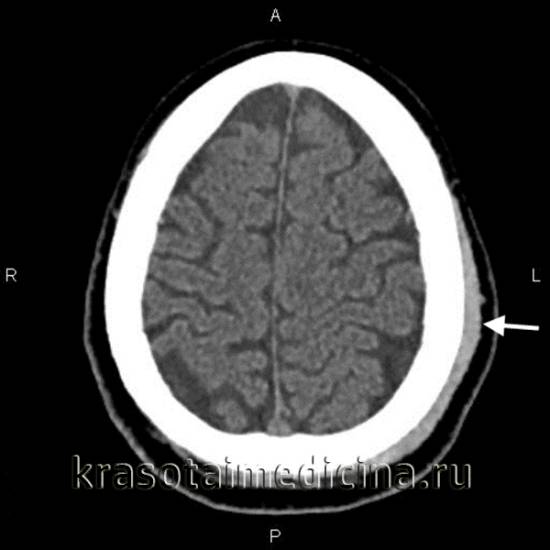

image

КТ головного мозга. Гематома периферических мягких тканей левой теменной области